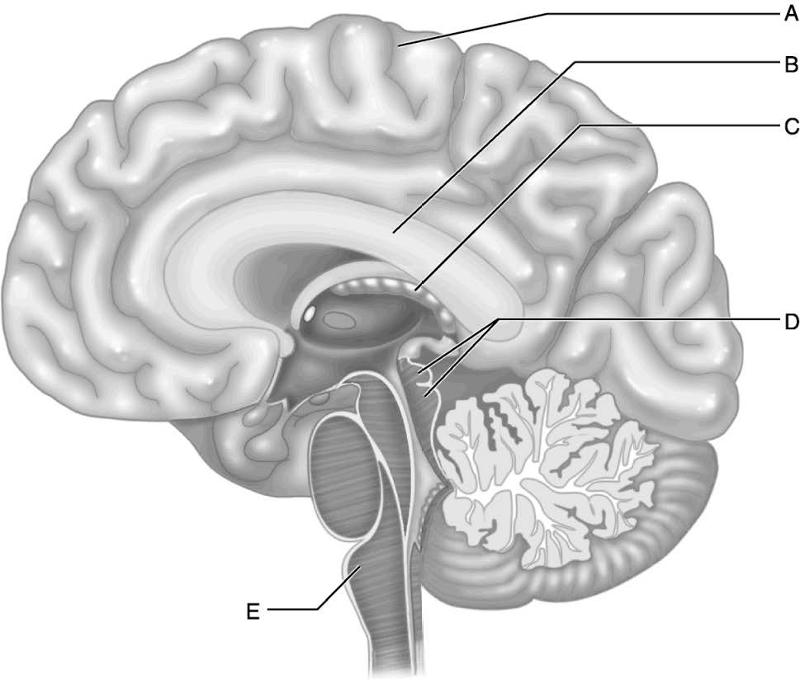

Which letter indicates the primary visual cortex, which receives

information from neurons in

the retina of the eye?

A)

A

B) B

C) C

D) D

E) E

Which letter indicates Broca's area, which controls the motor

movements necessary for

speaking?

A) A

B) B

C)

C

D) D

E) E

Which letter indicates Wernicke's area, which is important for

understanding spoken words?

A) A

B) B

C) C

D)

D

E) E

Which letter indicates an area that is characterized by huge neurons

known as pyramidal cells?

A) A

B) B

C) C

D)

D

E) E

Which letter indicates the primary somatosensory cortex?

A)

A

B) B

C) C

D) D

E) E

Which letter indicates the corpora quadrigemina, meaning "four

bodies?"

A) A

B) B

C) C

D) D

E) E

Which letter indicates the medulla, the functional neural connection

between the pons and the

spinal cord?

A) A

B) B

C)

C

D) D

E) E

Which letter indicates the region of the brain that has the greatest

surface area due to the

numerous surface convolutions?

A)

A

B) B

C) C

D) D

E) E

Which letter indicates a choroid plexus, which produces cerebrospinal

fluid (CSF)in all four

ventricles of the brain?

A) A

B)

B

C) C

D) D

E) E

Which letter indicates the corpus callosum, which is an area of white

matter where axons

from one cerebral hemisphere cross the midline

to the opposite hemisphere?

A) A

B) B

C) C

D)

D

E) E